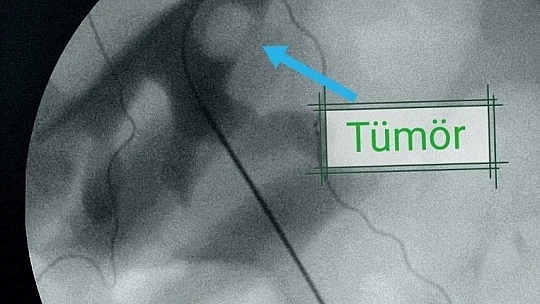

3 çocuk 1 torun sahibi 54 yaşındaki Fuat Salar, 1988 yılında trafik kazası sonrası geçirdiği rahatsızlık ve ameliyatın ardından sol böbreğini kaybetti. Bir yıl sonrasında ise sağ böbreğinden açık taş ameliyatı olan Salar, en son bir ay önce idrar yapamama şikayeti ile Medical Park Elazığ Hastanesi’ne başvurdu. Burada Üroloji Uzmanı Op. Dr. Serhat Yentür’ün tedavisine başladığı Salar, yapılan tetkikler sonucunda böbreğinde 3 santimetrelik lezyon ve tümöral hücreler saptandı. Bunun üzerine zor ve riskli olan ‘Perkütan’ yöntemi ile operasyon planlandı. Operasyonda Salar’ın böbreğine yandan girilip orada bir tüp oluşturulduktan sonra böbreğin içine girildi. Ardından hastadaki tümör tur aletleriyle kazındı. Başarılı geçen ameliyatın ardından Salar, 3 gün sonra taburcu edilirken, perkütan yöntemi ile dünya literatüründe 84’üncü vaka olarak kayıtlara geçtiği öğrenildi.

Yapılan tetkikler sonucunda hastanın nadir uygulanan yöntemle sağlığına kavuştuğunu ifade eden Op. Dr. Serhat Yentür, "Hastamıza kontrastsız emar (MR) çektik. MR’de sol böbreğin ana çıkış alanında 3 santimetrelik bir lezyon görüldü. Yani böbrek içinde bir tümör vardı ve onun temizlenmesi lazımdı. Normal şartlarda iki böbreği sağlıklı olan insanda bu böbreği alırız. Ama bu hastamız, tek böbrekli olduğu için böbreği aldığımız zaman hasta direkt diyalize bağlı kalacaktı. Hastamıza bir şans tanıdık ve dünyada çok nadir yapılan bir yöntemi uygulamaya karar verdik. Bu yöntem böbreğe yandan girilerek orada bir tüp oluşturup böbreğin içine perkütan yöntemi ile girilmesinin ardından tümörü tur aletleriyle kazıma işlemiydi. Bu yöntem ve teknikle ameliyat yaptık ve çok başarılı oldu. Hastamız da takiplerine geldi ve gayet iyi. Kreatinlerinde de artma olmadı. Böbreği koruyarak bu ameliyatı başarılı bir şekilde yapmış olduk. Şimdiye kadar dünyada 83 tane bununla ilgili bildirilmiş vaka var, bizim hastamız 84’üncü oldu. Bunu Elazığ’da Medical Park Hastanesi’nde yaptık ve hastamız gayet iyi durumda. Ameliyattan 3 gün sonra hastamızı ayakta taburcu ederek evine gönderdik. Ameliyattan sonra tekrar orada tümör çıkmaması için böbrekten girdiğimiz alandan ilaç uygulaması yaptık. Her şey istediğimiz gibi gitti. Hastamızın tetkikleri temiz, bundan sonra da kontrollerine devam edeceğiz” diye konuştu.